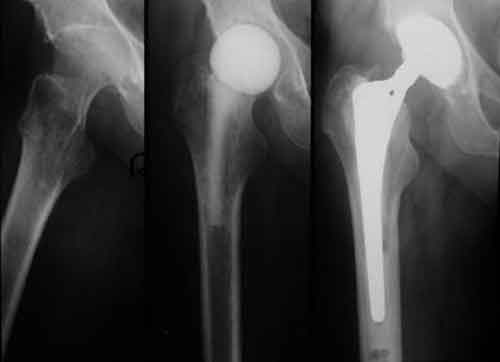

Artroplastica: decorso post-operatorio preferito con terapia acquatica

Nonostante il crescente ricorso a interventi come l’artroplastica totale dell’anca (THA) e l’artroplastica totale del ginocchio (PTG), non si e’ ancora raggiunto un’opinione condivisa sul trattamento ottimale postoperatorio. La terapia acquatica, tra le altre.

“Il nostro e’ uno dei pochi studi che dimostrano un effetto clinicamente rilevante sulla qualita’ della vita dopo PTG di un fattore che puo’ essere influenzato dal professionista sanitario. L’intervento e’ semplice da gestire e richiede un limitato impegno aggiuntivo del sanitario”. Nello studio alcuni pazienti sono stati assegnati in modo casuale a ricevere la terapia acquatica con inizio o 6 giorni o 14 giorni dopo l’intervento. In entrambi i gruppi, la terapia e’ durata 30 minuti, tre volte alla settimana, fino alla quinta settimana post-operatoria. La funzione fisica, il dolore e la rigidita’ sono stati valutati 3, 6, 12 e 24 mesi dopo la procedura. Dopo l’artroplastica dell’anca, tutte le misure a ogni follow-up sono risultate migliori nei pazienti che hanno iniziato la terapia acquatica dopo che la ferita era guarita. Al contrario, tutti i risultati medi sono stati migliori nel gruppo che ha iniziato la terapia 6 giorni dopo artroplastica del ginocchio. “THA ha un alto tasso di soddisfazione dei pazienti, e i pazienti riferiscono una migliore qualita’ della vita dopo la procedura. In questi casi interventi aggiuntivi, come l’inizio della terapia acquatica, non possono portare a un grosso miglioramento”, ha ipotizzato Liebs. “Dopo PTG, i pazienti sono meno soddisfatti, per cui l’intervento aggiuntivo ha un effetto maggiore”.